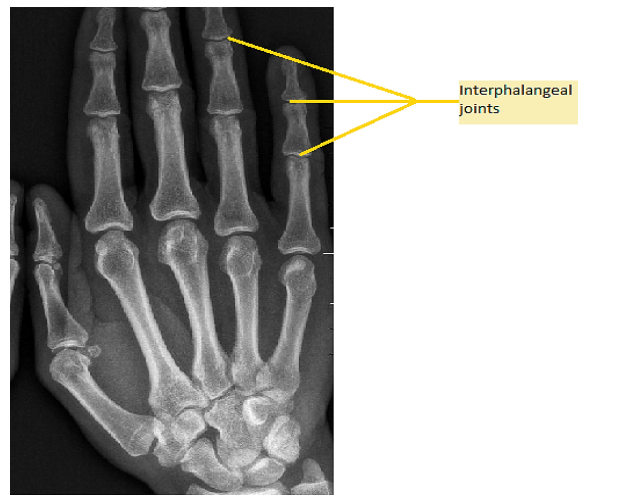

Hint: A joint in a human body is the connection between two bones. It is of three main types (immovable, slightly movable, and freely movable) based on whether it allows movement or not. Interphalangeal joints are present between the phalanges (bones in the thumb and fingers).

Option (B) is correct. Hinge joints function much like the hinge of the door thereby allowing movement of the bones only in one direction back and forth further restricting the movement in other planes. These joints are present in fingers, toes, elbows, knees, and ankles. Since interphalangeal joints are known to be present in fingers and toes (made of phalanges) that provide movement of the bones towards the palm and foot therefore these interphalangeal joints are also called hinge joints.

Note: The hinge joint is that joint in which the two bones are connected by these joints that allow movement only in one direction. The interphalangeal joints are called hinge joints because these allow movement of the phalanges only in one direction.